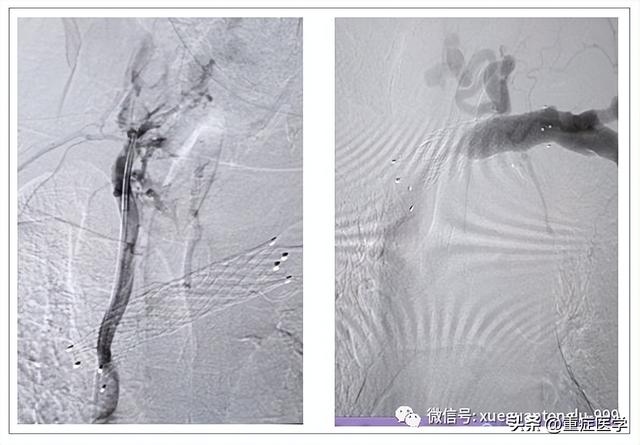

1、如果导丝进入小的血管,或者血管局部狭窄时;此时如果扩张,可引起导丝扭结、或者血管破裂、或者导管异位、或者拔除扩张管困难,建议扩张血管有异常阻力时,需要寻找异常阻力的原因,必要时采用介入下诊断、治疗。

2、“麻花导丝”形成(如下图所示),导致扩管困难。其形成原因:静脉内有狭窄、静脉扭曲、导丝进入细小静脉、扩皮粗暴、导丝入皮肤处的皮下筋膜未完全切开、动脉鞘扩张不理想、导丝进入过深比如三尖瓣、导丝未在血管内等原因。

最后,在置管的过程中,我们需要小心导丝滞留体内的发生(如下图所示)。根据国外的文献报道,即使是圣路易斯华盛顿大学麻醉系这样知名的地方,也都发生过导丝滞留的错误,实在令人吃惊。所以,在穿刺、扩管、置管中要确保导丝末端在体外,在完成置管后,需要清点穿刺包内器械,至少包括导丝、扩张导管和穿刺针。